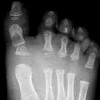

Рентгенография стоп с нагрузкой ребенку

Рентгенография ног с нагрузкой ребенка дает представление о структуре и функциях всех костных и суставных образований стопы. Рентгенография стоп с функциональной нагрузкой выполняется, стоя на исследуемой ноге. в то время как противоположная нога согнута в коленном суставе. В детской травматологии и ортопедии рентгенологическое исследование стопы с нагрузкой у ребенка показано для диагностики продольной и поперечной стопы, вальгусных деформаций стопы, остеоартрита, артрита и травм стопы. Рентгенограммы обеих стоп в прямой и боковой проекциях, выполненные при ортостатическом стрессе, имеют решающее диагностическое значение.